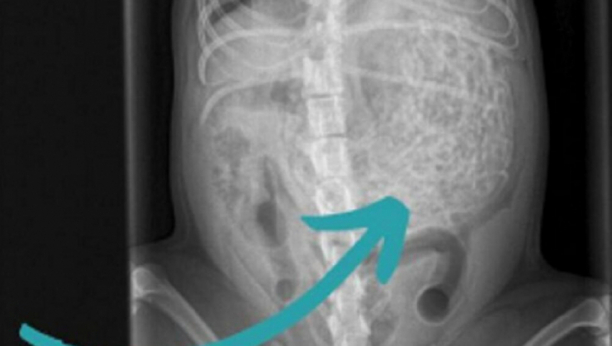

Veterinarski pregled pokazao je da pas ima nešto neobično u stomaku, pa su se odmah odlučili za operaciju. Izvađeno mu je oko 60 gumica teških 200 grama, a pas Hem ima samo šest kilograma.

Na ultrazvuku je otkriveno da je pas pojeo 200 grama gumica za kosu!